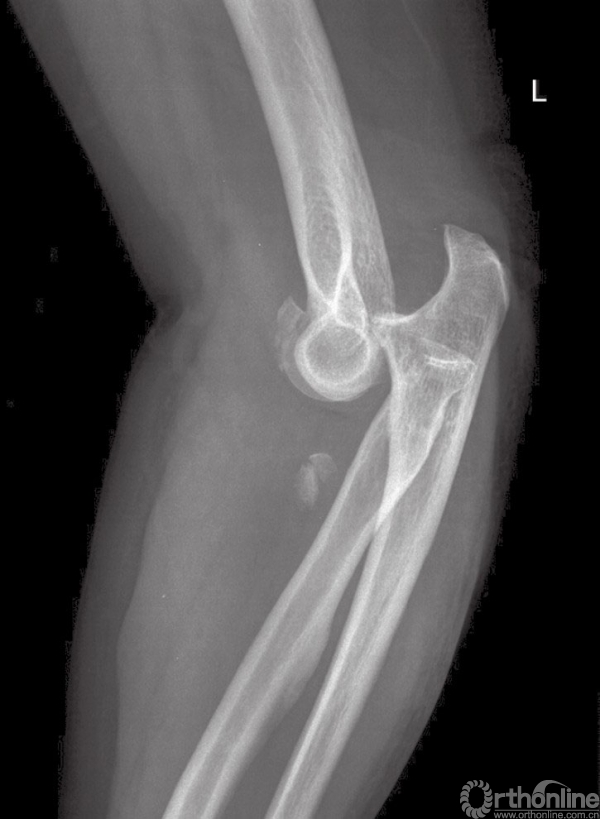

初始治疗措施包括局麻下闭合复位并用夹板固定。手术治疗依据复位后拍摄的肘关节前后位及侧位X线片,常规进行CT检查,通过CT扫描可以直观地了解冠状突及桡骨头的骨折大小及范围。同时行三维CT检查对评估损伤也十分有帮助(图2)。

图2 侧位片提示肘关节脱位,桡骨头骨折,冠状突Ⅲ型骨折